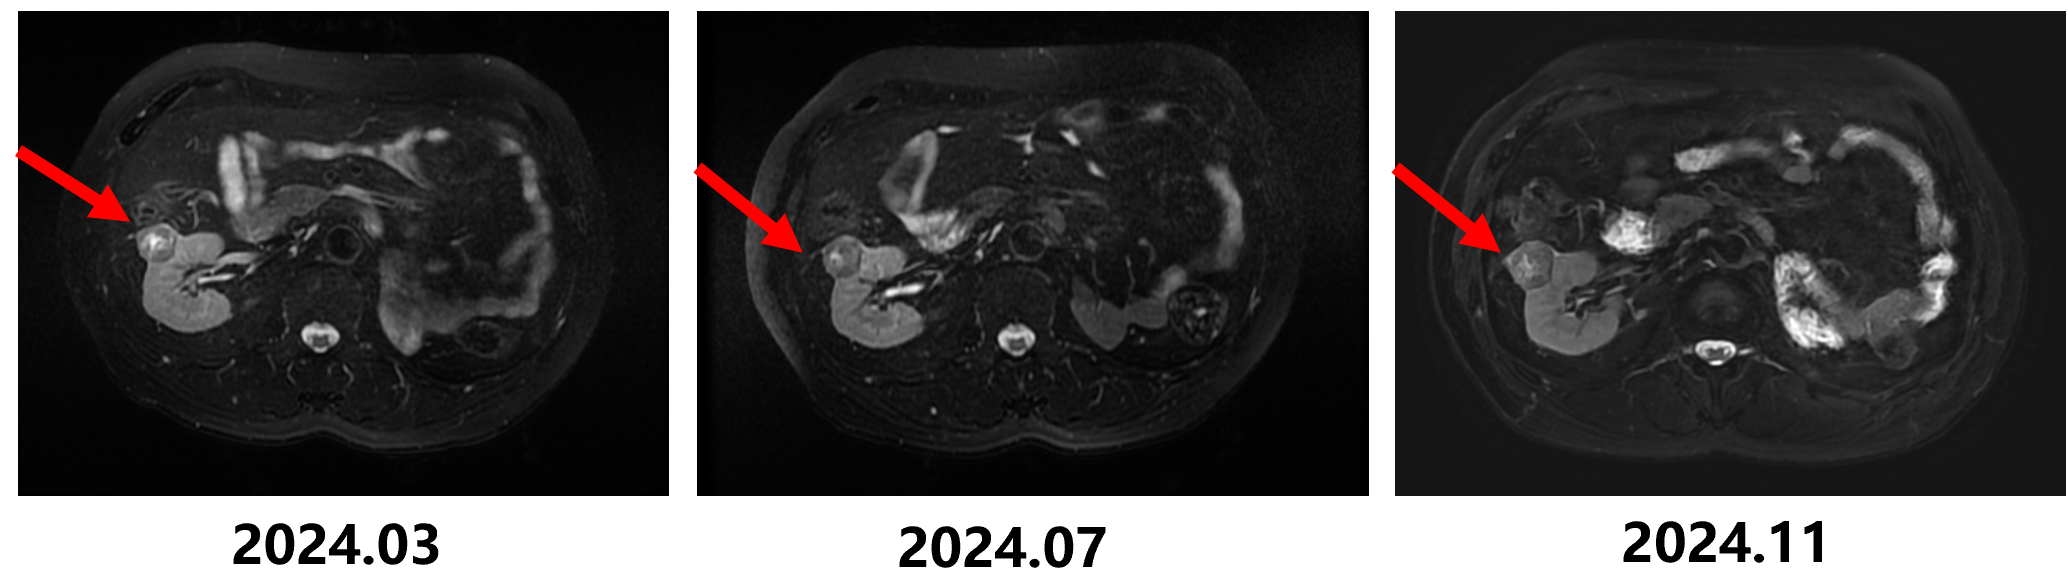

2024-03-21 MRI示:左肾术后改变; 右肾数个类圆形异常信号,肿瘤可能,后行特瑞普利治疗。

2024-07-05 MRI示:右肾数个类圆形异常信号,肿瘤可能,较前(2024-3-20)弥散信号减低。

2024-11-15 MRI示: 右肾数个类圆形异常信号肿块、结节影,考虑肿瘤性病变,较前(2024-07-04)部分增大。